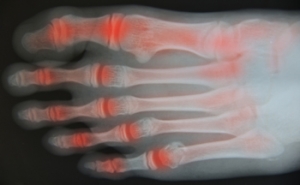

- Arthritis (such as Gout, Rheumatoid, and Osteoarthritis)

To figure out the cause of foot pain, podiatrists utilize several different methods. This can range from simple visual inspections and sensation tests to X-rays and MRI scans. Prior medical history, family medical history, and any recent physical traumatic events will all be taken into consideration for a proper diagnosis.

Managing Foot Arthritis

Osteoarthritis, or OA, is a chronic condition that involves the deterioration of the cartilage in joints over time, leading to pain and stiffness. The foot, with its numerous weight-bearing joints, is a common location for OA to develop. Symptoms of foot OA may include aching, reduced range of motion, pain in the ball of the foot or heel, joint soreness, stiffness, and joint swelling. Without proper treatment, foot OA can lead to complications such as bunions, calluses, corns, and arthritis in the big toe joint. Range of motion exercises and foot stretches can strengthen foot muscles and improve symptoms. Wearing proper footwear and shoe insoles, and a diet rich in omega-3 fatty acids, vitamin D, and calcium can help reduce inflammation and joint pain. Maintaining a moderate weight also helps reduce pressure on the foot joints. If you have foot arthritis, it is strongly suggested that you make an appointment with a podiatrist who can provide individualized treatment to alleviate your discomfort.

Arthritis is a term that is commonly used to describe joint pain. The condition itself can occur to anyone of any age, race, or gender, and there are over 100 types of it. Nevertheless, arthritis is more commonly found in women compared to men, and it is also more prevalent in those who are overweight. The causes of arthritis vary depending on which type of arthritis you have. Osteoarthritis for example, is often caused by injury, while rheumatoid arthritis is caused by a misdirected immune system.